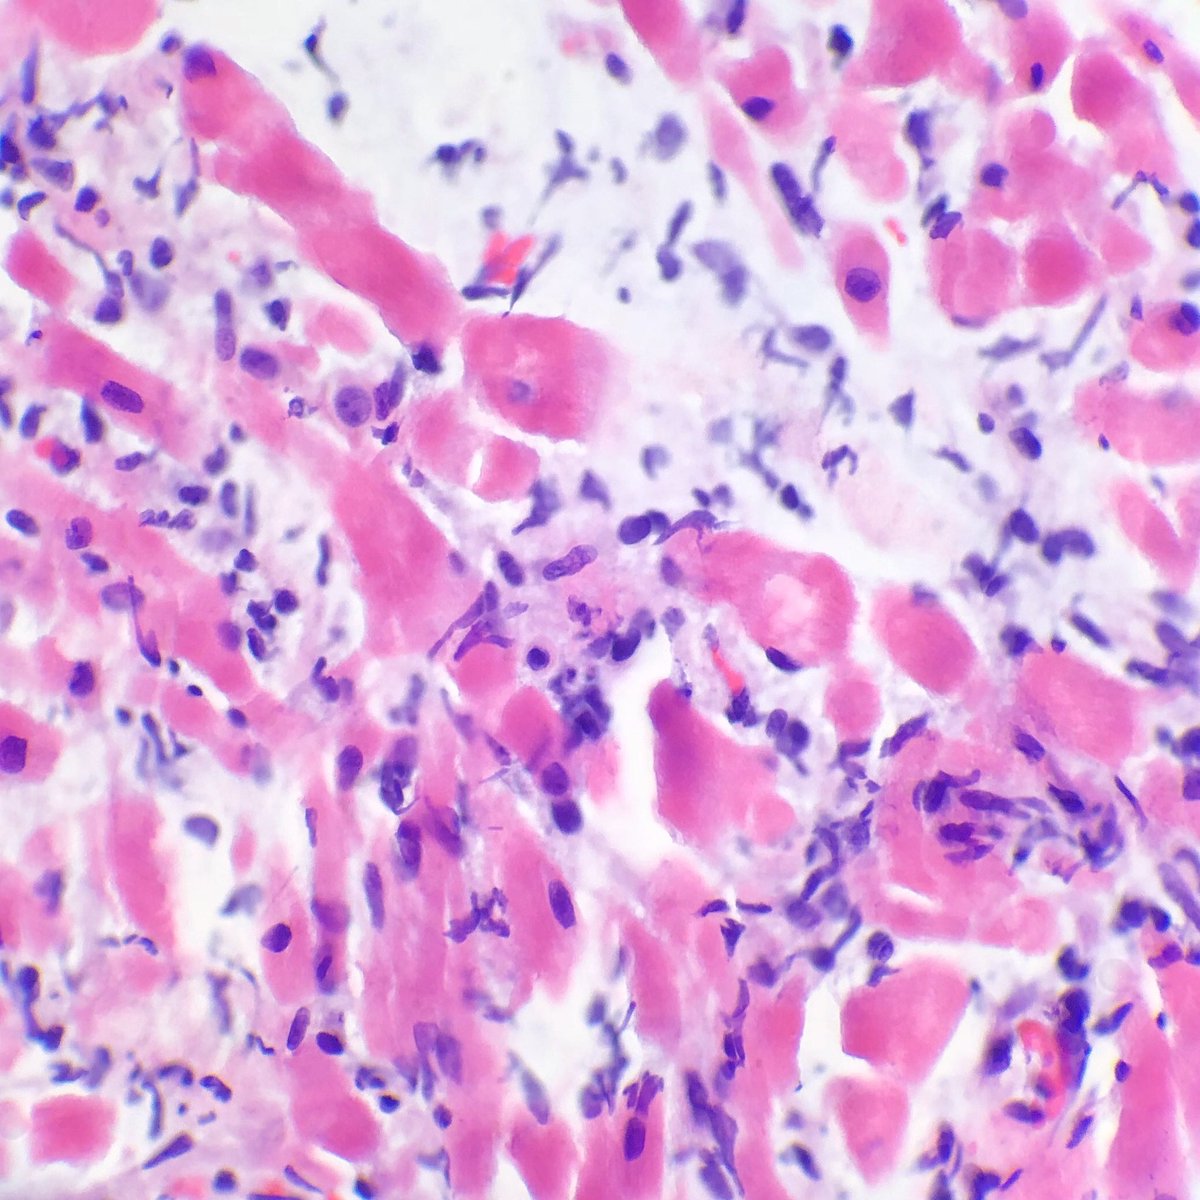

Межуточный миокардит: гистологические исследования

Раздел: Идеи и советы